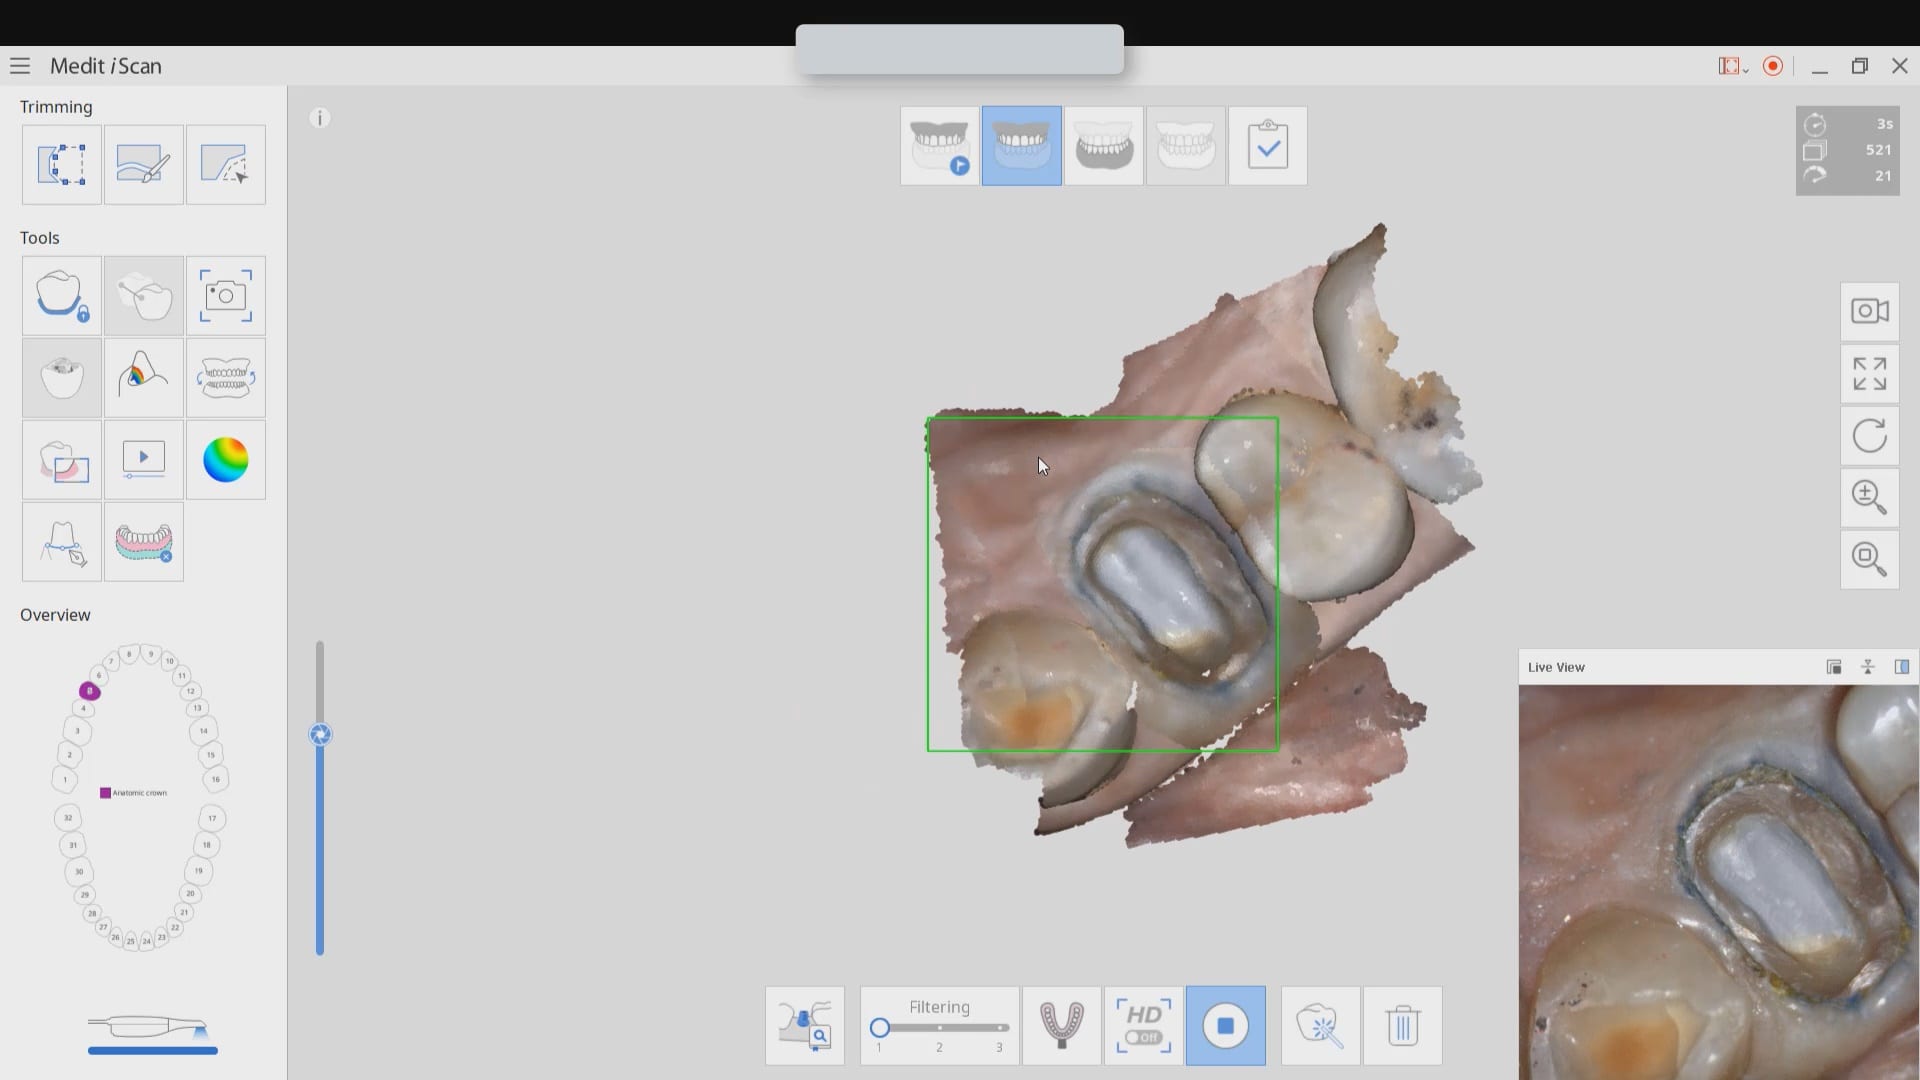

Case set up involved imaging the pre-existing condition in the pre-op catalog box. Excess information was cropped to reduce file size. The data was then copied to the maxillary arch catalog box and the area to prepared was edited out in preparation for final optical impressions.